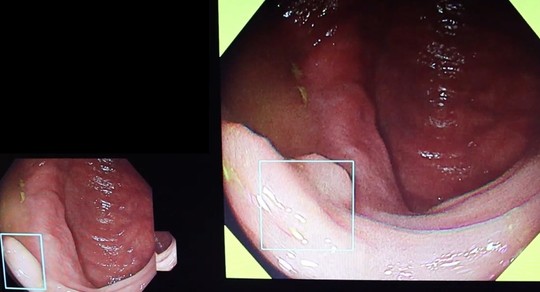

桐山クリニックでは、AI(人工知能)内視鏡診断支援システムEndoBRAIN(ワンモニター型)を導入しました。大腸内視鏡検査中にポリープの存在をAI技術により瞬時に検出できます。大腸内視鏡全例で使用できる体制を整えています。

従来システムは内視鏡検査画像とEndoBRAIN用モニターがそれぞれ別となっていますが、当院で導入した最新システムは一つのモニター内で検査画像とAI画像を合わせて視認できるとても見やすいシステムです。

一つのモニターで検出と診断ができます(BOX型PC)

①病変をAIの目で瞬時に捕捉

経験豊富な内視鏡専門医の目に加えて、疲れ知らずのAIが大腸病変を瞬時に捕捉し追いかけます。